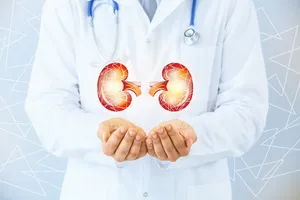

12. 신장결석

신장결석은 신장이나 요로에 돌이 생겨 소변 흐름을 방해하여 극심한 통증을 유발하는 질환입니다. 주로 옆구리나 허리 부위에서 느껴지기 때문에 허리 통증의 원인으로 오인될 수 있습니다. 혈뇨, 구역, 구토를 동반할 수 있습니다. 수분 섭취 부족, 식습관 불균형, 가족력 등이 원인으로 작용하며, 방치할 경우 신장 기능 손상을 초래할 수 있습니다. 치료는 결석의 크기와 위치에 따라 약물 치료, 체외충격파쇄석술, 수술 등 다양한 방법이 사용됩니다.